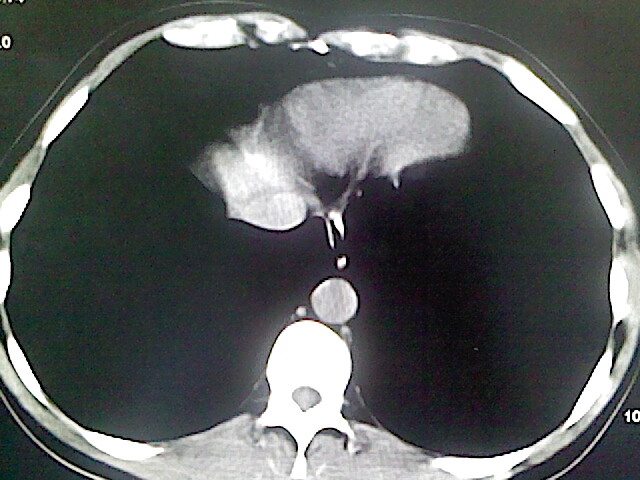

以下是引用卜一在2009-3-14 9:49:00的发言:[br]胆囊萎缩,胆囊壁不规则增厚,内部结构模糊,增强明显强化。另:肝左叶外侧段肝囊肿。支持:慢性胆囊炎!高度可疑:胆囊癌!

以下是引用余辉在2009-3-14 8:48:00的发言:[br]1)慢性胆囊炎。2)肝左叶外侧段肝囊肿。3)脂肪肝。[br]支持,胆囊萎缩,密度增高,不知b超具体有何提示,钙胆汁?结石?

以下是引用jiangjing在2009-3-14 10:18:00的发言:[br]1)慢性胆囊炎。2)肝左叶外侧段肝囊肿。3)脂肪肝。4.】建议行肝功能检查